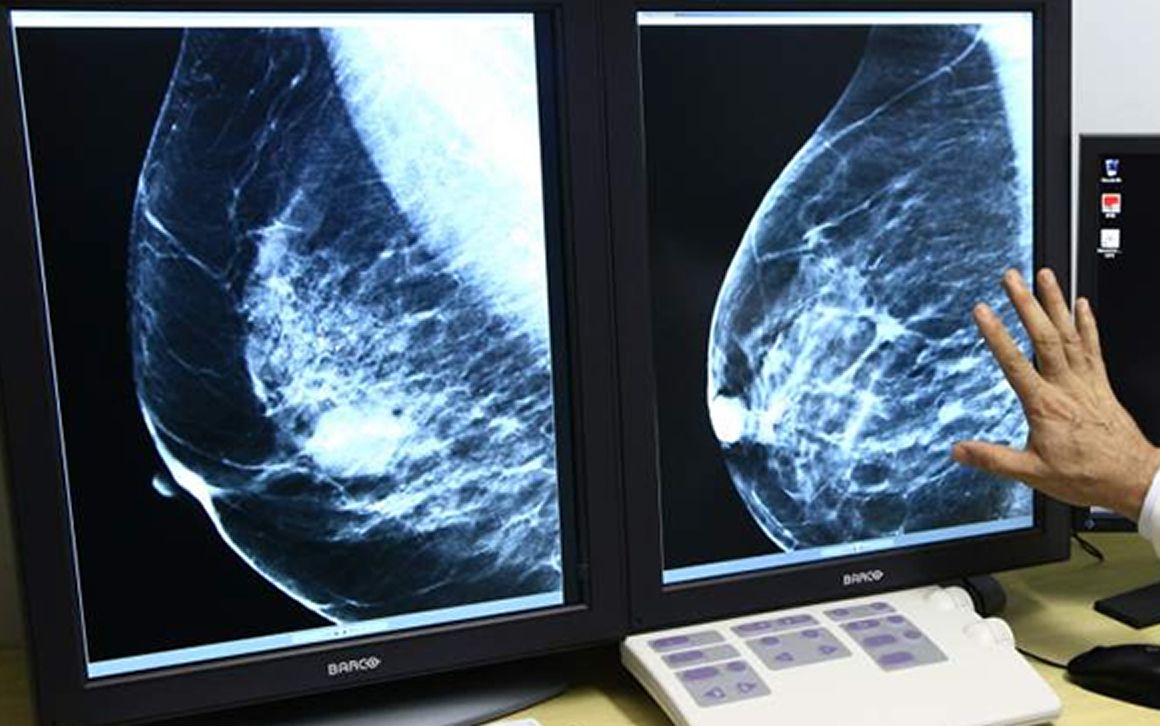

"La selección anual a partir de los 40 años es la mejor estrategia para prevenir una muerte temprana de cáncer de mama"

“La selección anual a partir de los 40 años es la mejor estrategia para prevenir una muerte temprana de cáncer de mama”, asegura la investigadora que ha liderado el estudio, Elizabeth Arleo. De hecho, el argumento de que las mamografías con una periodicidad anual salvan más vidas no es nuevo. Instituciones como la American Cancer Society y el U.S. Preventive Services Task Force, admiten que comenzar las pruebas a los 40 ayuda a detectar más precozmente el cáncer de mama, pero también sostiene que las mamografías a esa edad producen también una mayor proporción de falsos negativos. El nuevo estudio ha utilizado datos de modelos informáticos para comparar los beneficios y riesgos de tres tipos de cribado. Las mamografías anuales a partir de los 40 años también llevarán a que se detecten los falsos negativos.

En este sentido, Otis Brawley, médico jefe de la American Cancer Society, sostiene que para una mujer de 40 años a la que se le practica este prueba, las probabilidades de obtener un falso negativo son “muy altas”, mientras que las probabilidades de que la mamografía le salve la vida “son muy pequeñas”. Esa relación riesgo / beneficio comienza a cambiar alrededor de la edad de 47 o 48 años, dijo, cuando los beneficios de la detección superan el riesgo de sobrediagnóstico.

Por ese motivo, la asociación estadounidense sugiere mamografías anuales a partir de los 45 años. El U.S. Preventive Services Task Force, por su parte, recomienda la revisión cada dos años a partir de los 50 años. Eso sí, ambos grupos recomiendan que las mujeres con un riesgo más alto se sometan a un cribado más temprano.